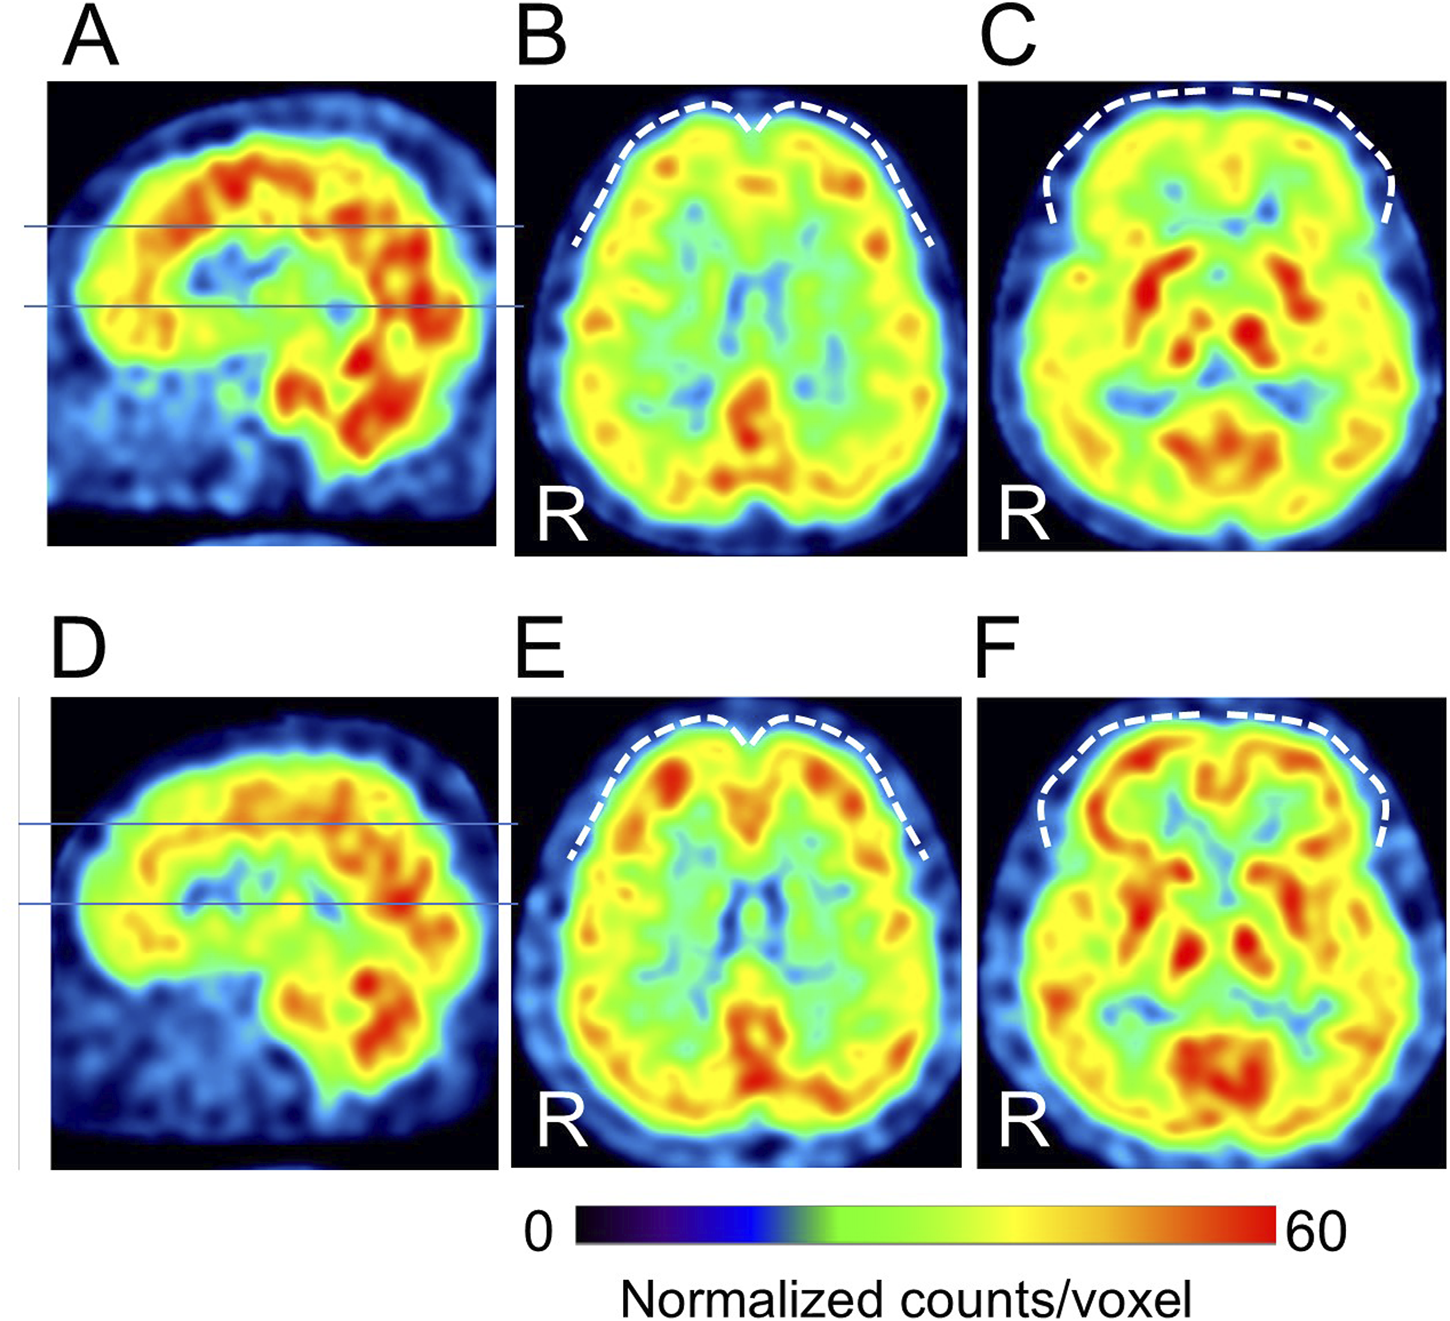

Cases with representative CBF-SPECT findings are shown in Figures 5–7. A patient in his 50s complained of low back pain before treatment and had relatively decreased frontal lobe CBF on CBF-SPECT images (Figures 5A–C). One year after ATX treatment, his symptoms improved, and CBF in the frontal lobe increased (Figures 5D–F). Figure 6 shows CBF-SPECT images of a patient in her 40s who presented with headache and orofacial pain before treatment. Pre-treatment CBF-SPECT (Figures 6A–C) showed that the CBF values in the subgenual anterior cingulate and precuneus were relatively higher than those in the surrounding frontal and parietal cortices. Two years after treatment with a dopamine system stabilizer, the symptoms improved, and the CBF in these regions decreased (Figures 6D–F). Figure 7 shows the CBF-SPECT images of a patient in her 50s with shoulder and upper limb pain before treatment. Her symptoms improved after ATX treatment, and her clinical condition remained stable 5 years later. Pre-treatment CBF-SPECT images showed relatively higher CBF in the insular gyrus (Figure 7A), which decreased in post-treatment images (Figure 7B).

Figure 5. A typical example of our cases with hypofrontal perfusion (dashed curves) in cerebral blood flow single-photon emission computed tomographic images (SPECT) before treatment (A–C), which is improved after treatment (D–F) (patient # 8). The lines in A and D indicate the axial levels of images (B, C, E, F). The voxel values are normalized by the mean number of counts per voxel in the cerebellum being 50; the color ranges from 0 to 60. R, patients’ right side. This case had no psychiatric comorbidities based on the Diagnostic and Statistical Manual of Mental Disorders, fifth edition. At the time of the pre-treatment SPECT, the patient was taking 100 mg/day of tramadol hydrochloride, and at the time of the post-treatment SPECT, the medications were 25 mg/day of atomoxetine, 10 mg/day of nitrazepam, and 0.25 mg/day of triazolam.

Figure 6. Representative images of cerebral blood flow single-photon emission tomography (SPECT) with typical findings that the subgenual anterior cingulate arrow in (A, C) and precuneus arrows in (B) show relative hyperperfusion before treatment (A–C), which decreases after treatment (D–F) (patient # 45). The lines in A and D indicate the axial levels of images (B, C, E, F). The voxel values are normalized by the mean number of counts per voxel in the cerebellum being 50; the color ranges from 0 to 70. R, patients’ right side. This case had no psychiatric comorbidities based on the Diagnostic and Statistical Manual of Mental Disorders, fifth edition. At the time of the pre-treatment SPECT, the patient was not taking any medications. At the time of the post-treatment SPECT, the medications were 10 mg/day of atomoxetine, 225 mg/day of venlafaxine, and 5 mg/day of zolpidem tartrate.